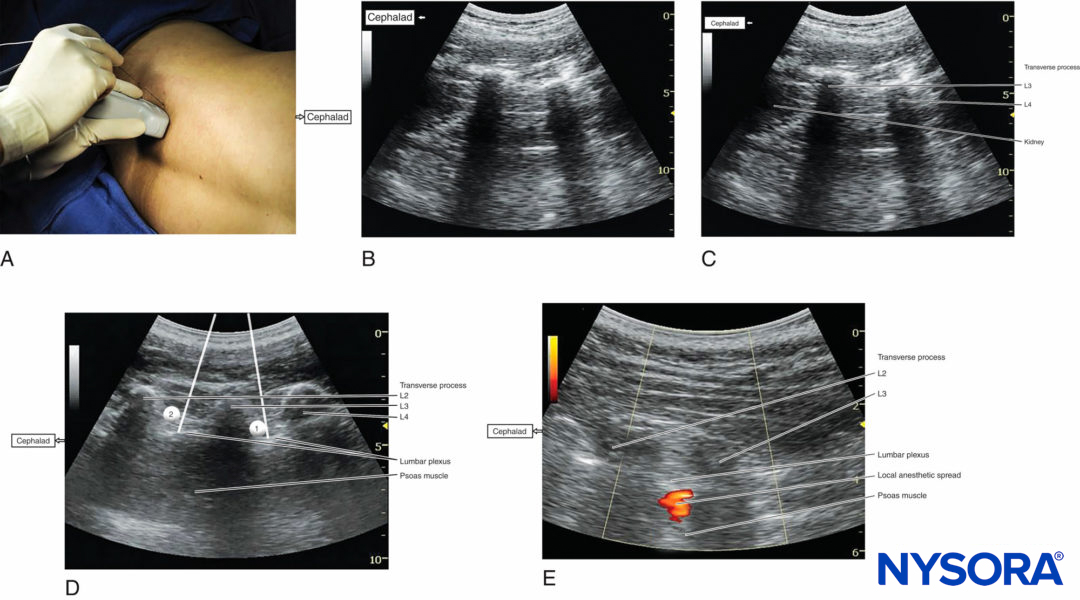

Once the transverse processes are recognized at approximately 4 cm lateral and parallel to the lumbar spine, to produce a longitudinal scan of the lumbar paravertebral region (Figure 4a), the psoas major muscle is imaged through the acoustic window of the transverse processes.

FIGURE 4. (A) Transducer position and needle insertion point to accomplish US-guided lumbar plexus block in the longitudinal parasagittal view using an out-of-plane approach. (B) US anatomy of the longitudinal lumbar paravertebral space at the L2–L3 and L3–L4 levels demonstrating the lower pole of the kidney on the left side of the image at a depth of approximately 5 cm. (C) Labeled US image of Figure 4b. (Continued) (D) Simulated needle insertion paths (1, 2) to inject local anesthetic at two different levels to accomplish a lumbar plexus block using an out-of-plane technique. (E) Local anesthetic disposition during injection into the psoas muscle and the L2–L3 level. The spread of local anesthetic is often not well visualized using two-dimensional imaging.

The psoas muscle appears as a combination of longitudinal hyperechoic striations within a typical hypoechoic muscle appearance just deep to the transverse processes (see Figure 1c,d). Some hyperechoic striations may appear particularly intense and may mislead the operator to interpret them as roots of the lumbar plexus; therefore, the identification of the roots in a longitudinal scan is not reliable without nerve stimulation. This unreliability is partly because intramuscular connective tissues (eg, septa, tendons) within the psoas muscle are thick and may be indistinguishable from the nerve roots at such a deep location.

As the transducer is moved progressively cephalad, the lower pole of the kidney often comes into view as low as the level of L2–L4 (Figure 4b, c). The goal of the technique is to guide the needle through the acoustic window between the transverse processes (between the “teeth” of the “trident”) of L3–L4 or L2–L3 into the posterior part of the psoas major muscle containing the roots of the lumbar plexus.

Both out-of-plane (see Figure 4a) and in-plane approaches can be employed with the parasagittal longitudinal technique. After obtaining ipsilateral quadriceps muscle contractions, local anesthetic is injected (Figures 4d) with real-time visualization of the injection into the posterior part of the psoas major muscle (Figure 4e).